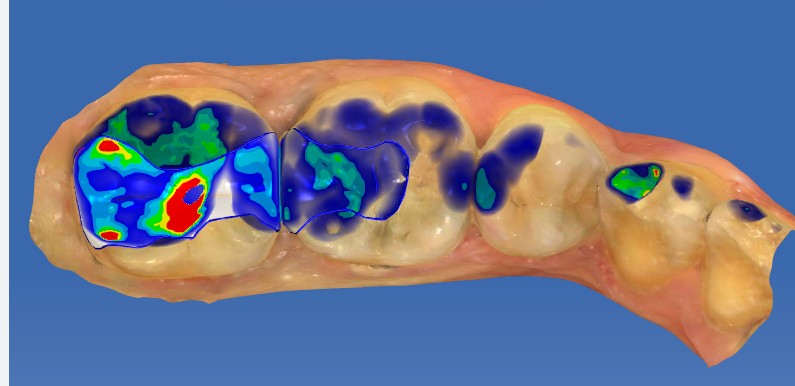

口腔检查时,会经常遇到以前补的银汞合金边缘变色,探有卡顿,形成了继发龋坏,建议重新充填或者瓷嵌体修复;瓷嵌体修复技术,可以非常好的恢复牙体形态和非常密合的边缘,色泽也非常逼真;我们采用CEREC(德国瓷睿刻)椅旁加工技术,达到最佳修复效果!